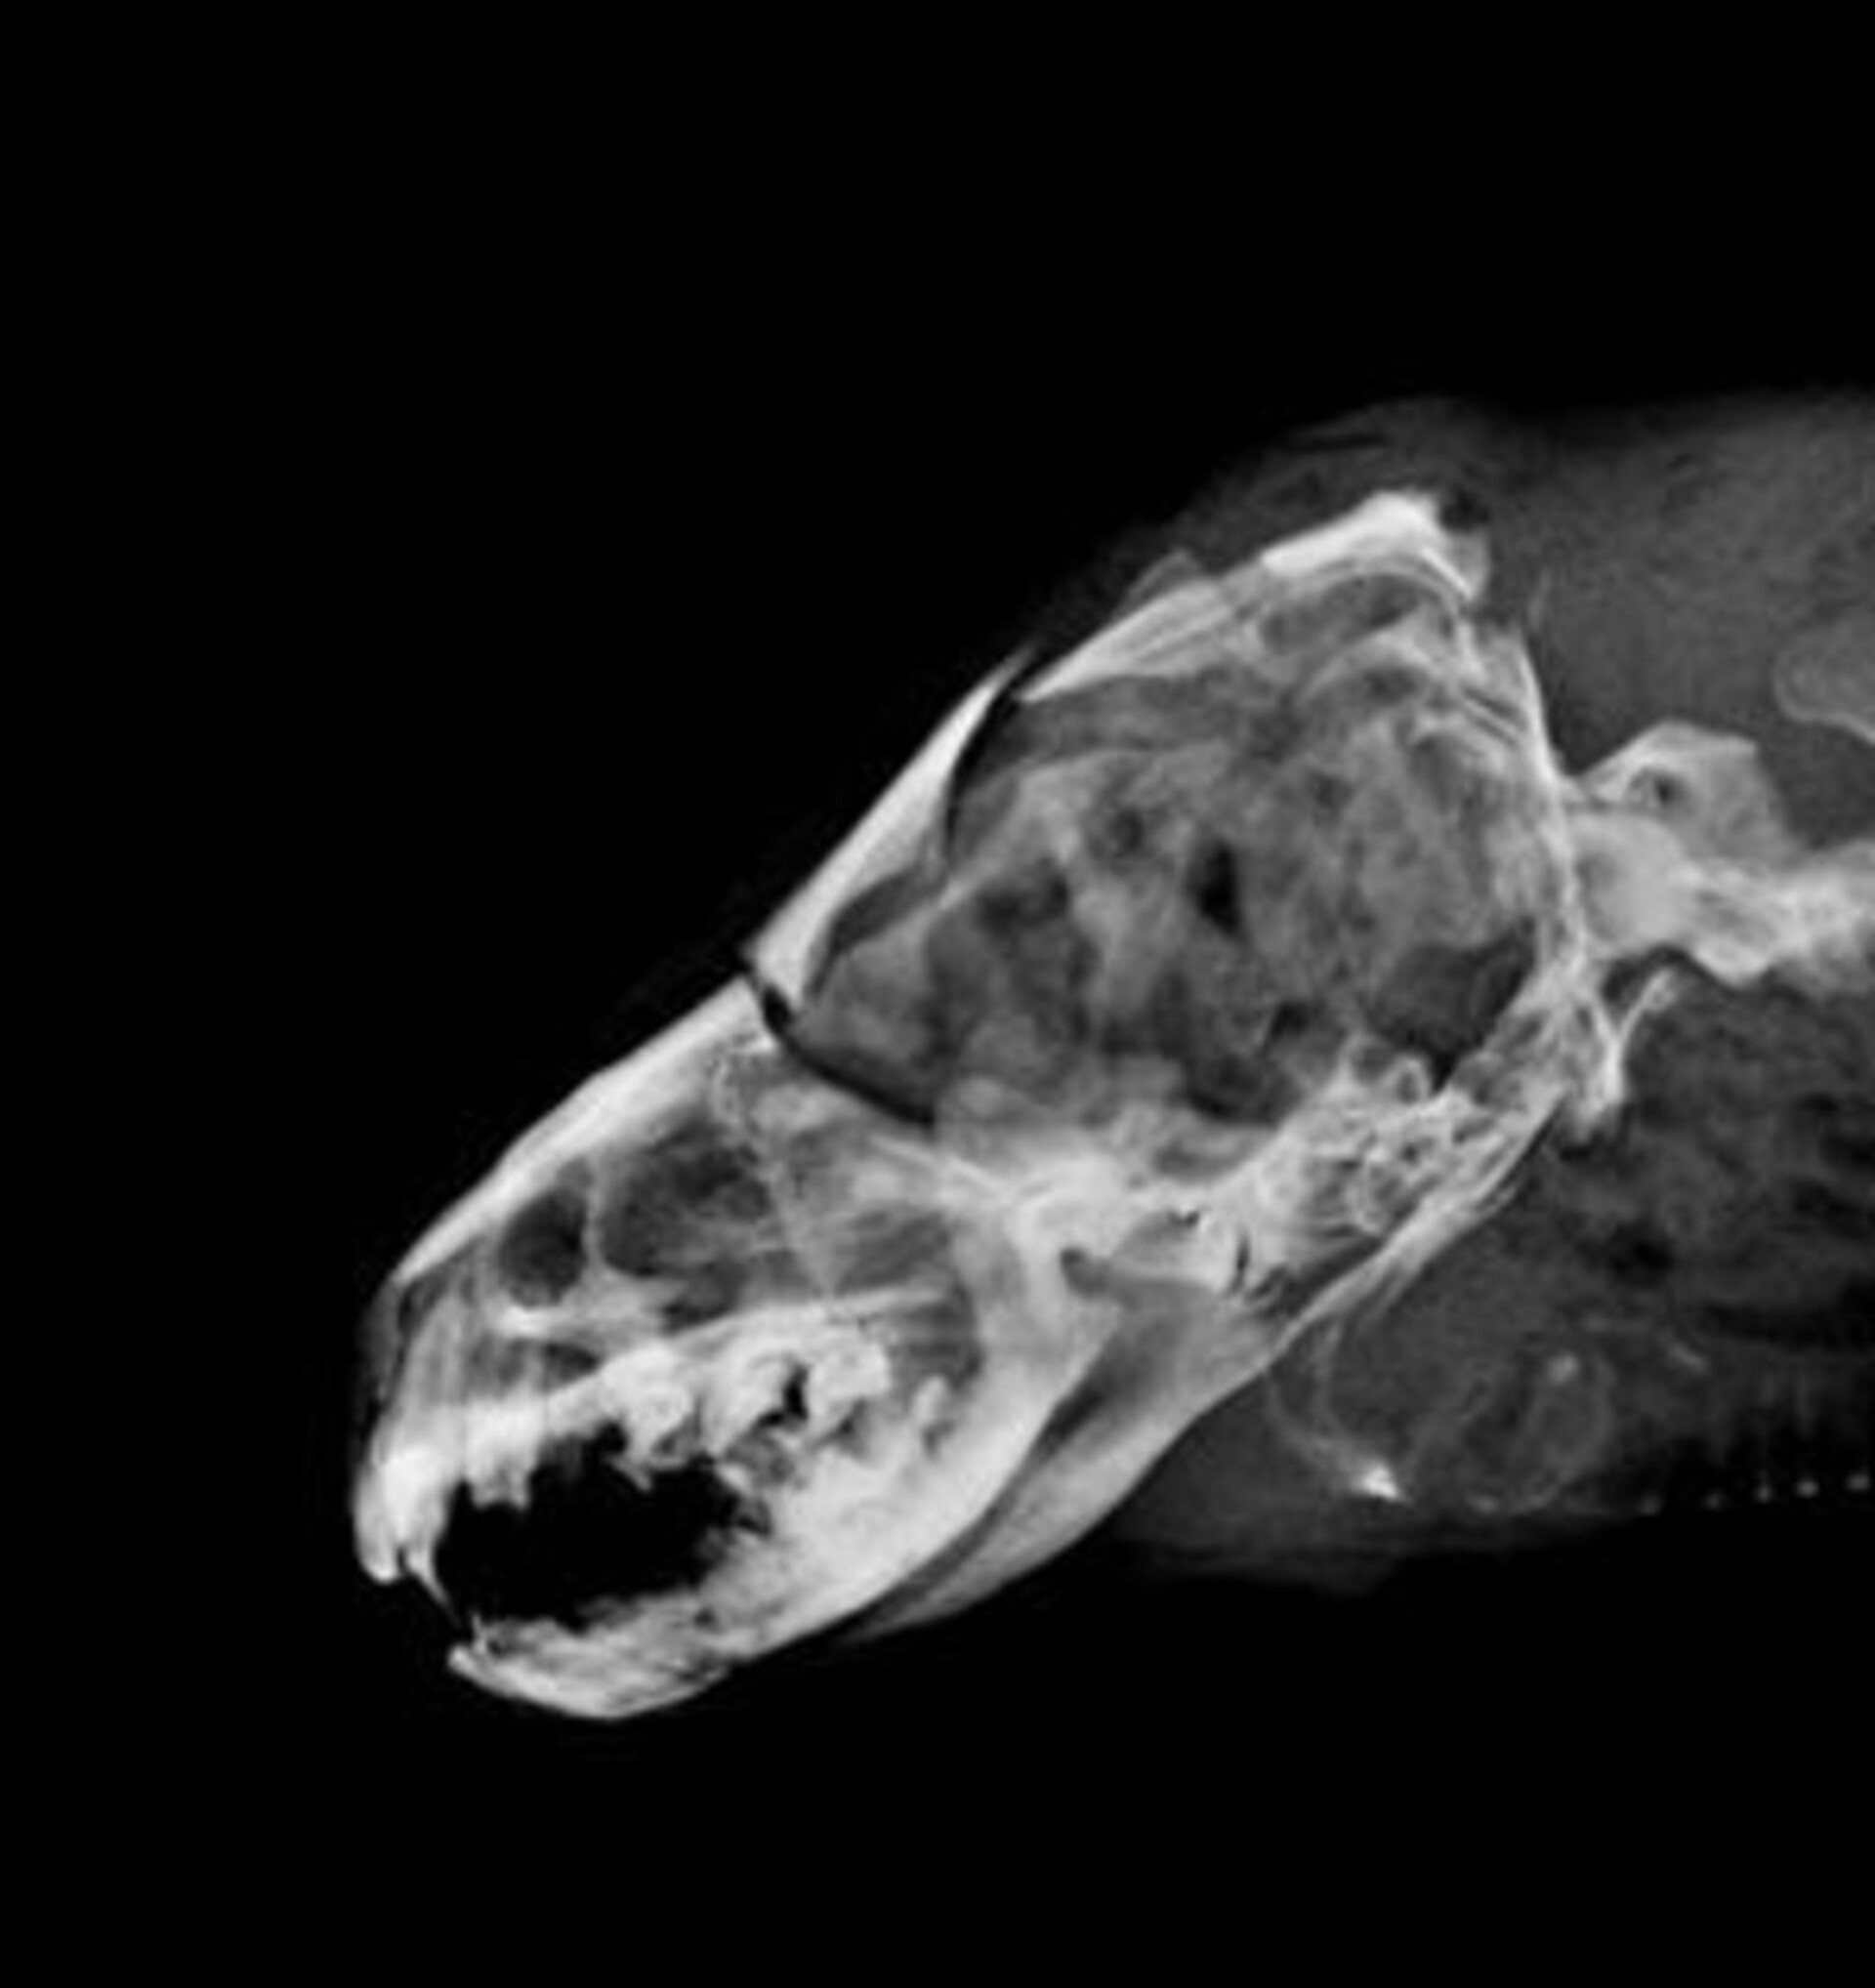

編號D105002水獺。成年雄性可見睪丸,體重5.95Kg,身長106cm、胸徑36.5cm,口鼻流大量鮮血,受理時仍為溫體但已無呼吸心跳。X光檢查頭骨粉碎性骨折、下頷骨骨折、肺前葉出血。死因判定為強烈外力撞擊頭部造成死亡。